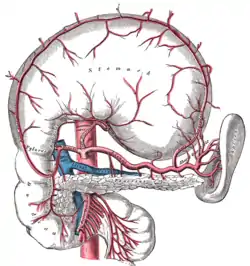

Blood supply

The duodenum receives arterial blood from two different sources. The transition between these sources is important as it demarcates the foregut from the midgut. Proximal to the 2nd part of the duodenum (approximately at the major duodenal papilla – where the bile duct enters) the arterial supply is from the gastroduodenal artery and its branch the superior pancreaticoduodenal artery. Distal to this point (the midgut) the arterial supply is from the superior mesenteric artery (SMA), and its branch the inferior pancreaticoduodenal artery supplies the 3rd and 4th sections. The superior and inferior pancreaticoduodenal arteries (from the gastroduodenal artery and SMA respectively) form an anastomotic loop between the celiac trunk and the SMA; so there is potential for collateral circulation here.

The venous drainage of the duodenum follows the arteries. Ultimately these veins drain into the portal system, either directly or indirectly through the splenic or superior mesenteric vein and then to portal vein.

Sections of the small intestine The celiac artery and its branches; the stomach has been raised and the peritoneum removed

The celiac artery and its branches; the stomach has been raised and the peritoneum removed Superior and inferior duodenal fossæ